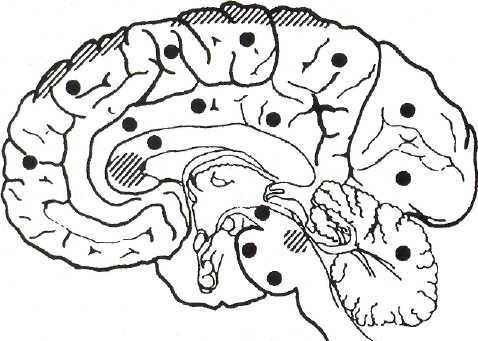

Рисунок 1 | Типичная локализация аксональных повреждений (черные кружки) и очагов геморрагии (заштрихованные участки). К. Bostrom, C.G. Helander (1986).

На характерной локализации повреждений и основана классификация диффузного аксонального повреждения мозга (Adams J. Н., 1989), которая часто используется патологами и лучевыми диагностами:

I тип — аксональные повреждения в белом веществе обоих полушарий большого мозга, мозолистом теле, мозговом стволе и мозжечке;

II тип — дополнительно к описанным изменениям имеются локальные повреждения в мозолистом теле;

III тип — в дополнение к перечисленным изменениям имеются локальные повреждения в дорсолатеральных участках ростральных отделов мозгового ствола.

Рисунок 1 | Типичная локализация аксональных повреждений (чёрные кружки) и очагов геморрагии (заштрихованные участки) (К. Bostrom, C.G. Helander, 1986).

- тип — аксональные повреждения в белом веществе обоих полушарий большого мозга, мозолистом теле, мозговом стволе и мозжечке;

- тип — дополнительно к описанным изменениям имеются локальные повреждения в мозолистом теле;

- тип — в дополнение к перечисленным изменениям имеются локальные повреждения в дорсолатеральных участках ростральных отделов мозгового ствола.